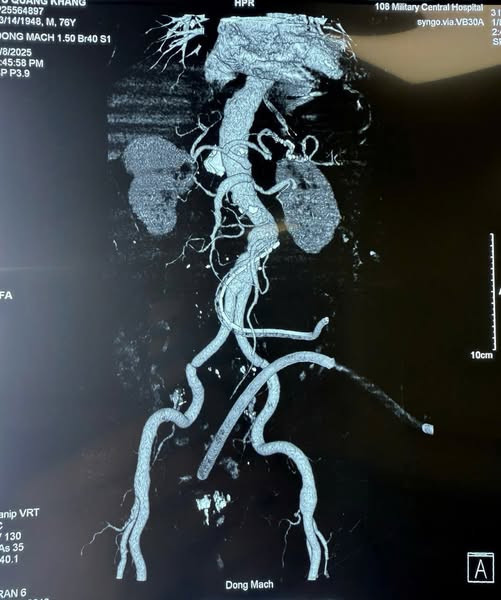

Kết quả chụp cắt lớp vi tính ổ bụng thấy hình ảnh khối phình động mạch chủ bụng đoạn dưới động mạch thận, có máu tụ và thâm nhiễm khoang sau phúc mạc và vùng tiểu khung.

| Phim chụp CT trước phẫu thuật cho thấy điểm vỡ và thấm máu xung quanh khối phình - Ảnh BSCC |